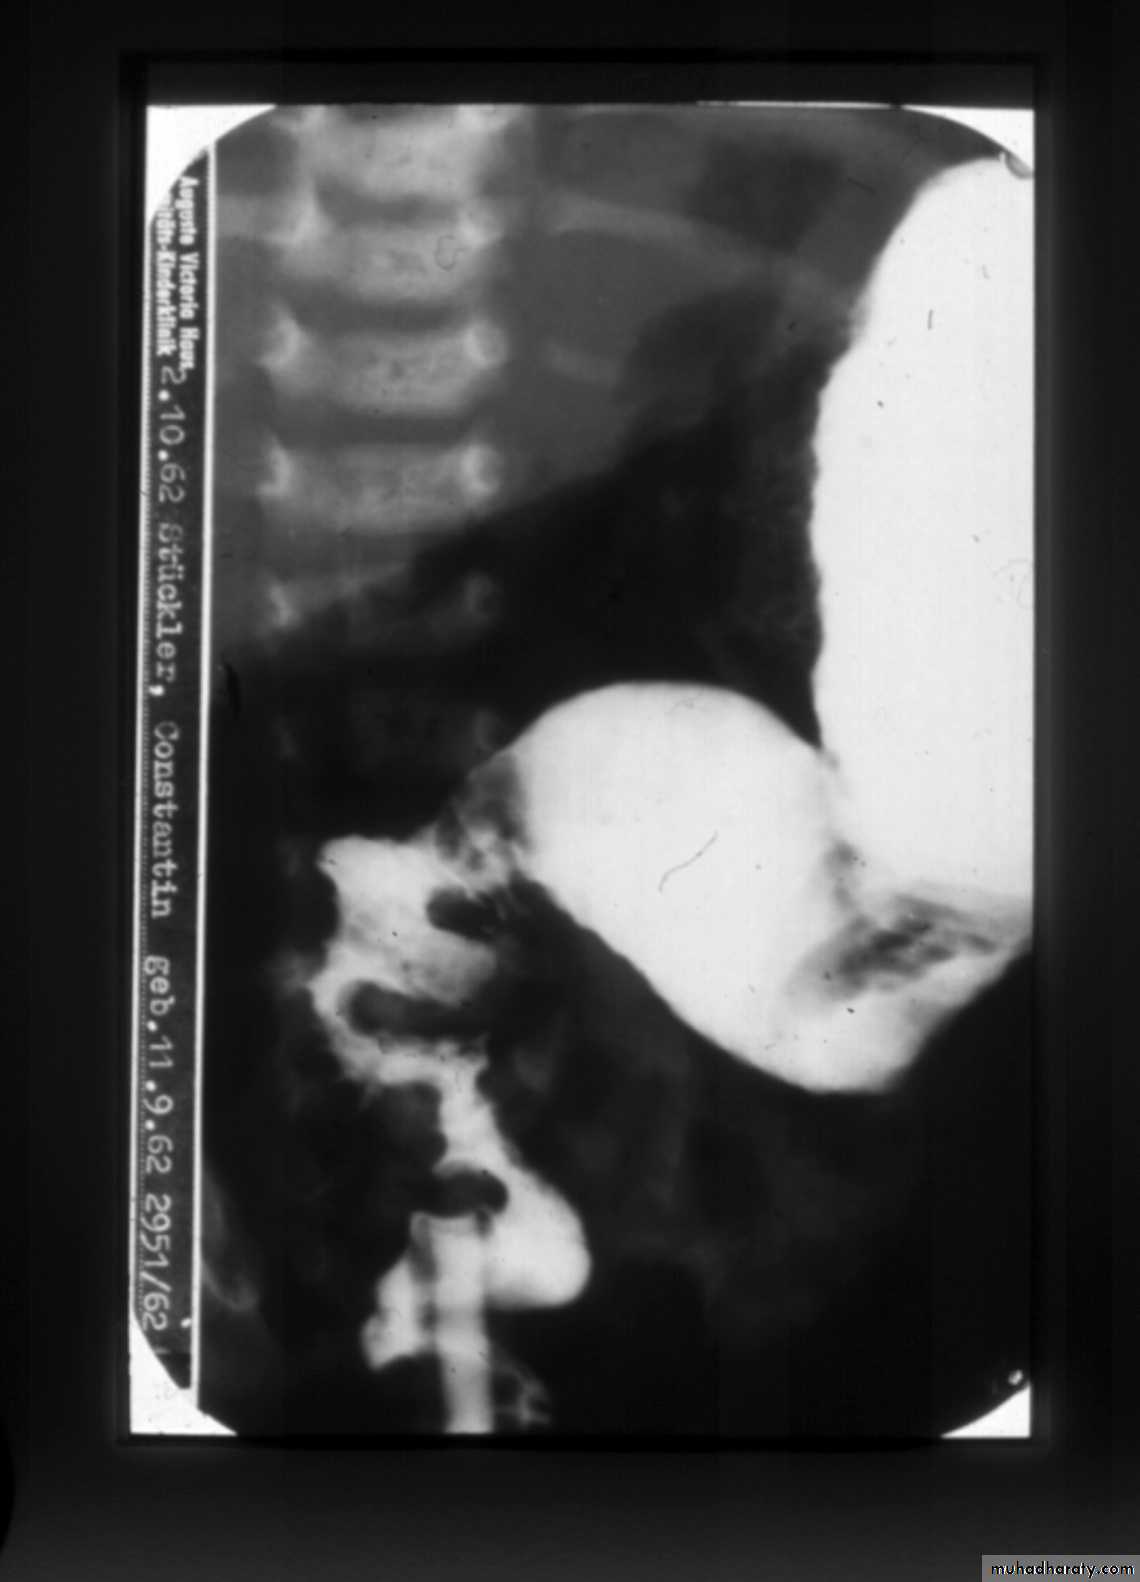

A 2 week old boy presents with history of constipation, abdominal distension and bilious vomiting. The pictures show the operative findings and radiographic investigation done for him.1. What is the diagnosis?2. What is the underlying pathology for this condition?3.Describe the findings in all slides.4. What other investigations used to reach the diagnosis?5. What are the steps of management for this condition?